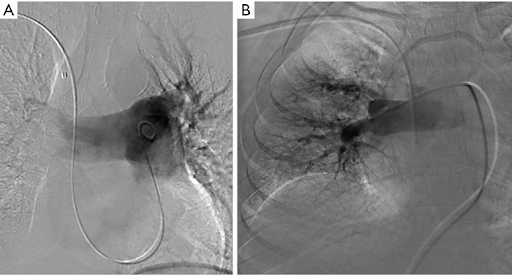

而对于管路和管道位置检测的金标准是胸部 X 光片,但需要医生手动检测,不仅留下了人为误检的可能,而且耗时较长。使用深度学习算法能够自动检测定位不当的导管和管路。而后发出警报,临床医生可以重新定位或移除它们,以避免危及生命的并发症。

该比赛的参赛者需要使用算法检测胸部 X 光片上导管和管路的存在和位置。使用机器学习在 40,000 张图像上训练和测试参赛模型,对放置不良的导管进行分类。